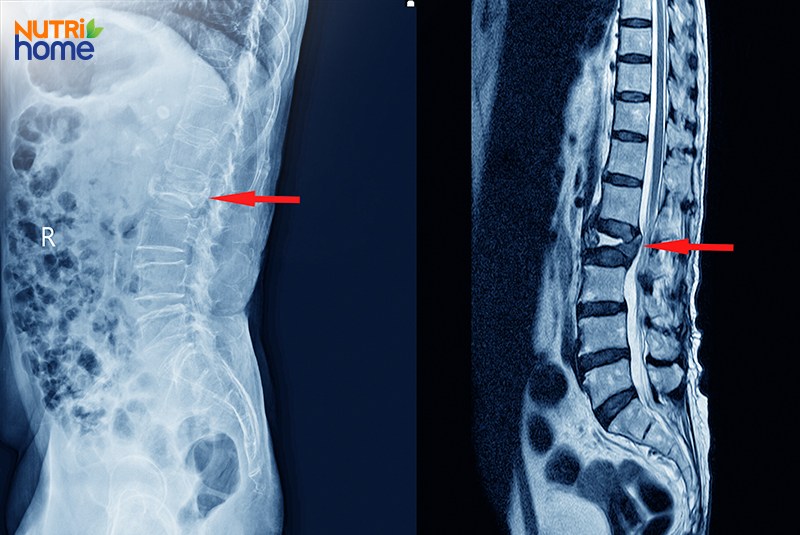

3.1. X-quang

Ảnh chụp X-quang chỉ hiển thị mô xương, không thể hiển thị thông tin về bao xơ và nhân nhầy bên trong đĩa đệm một cách chi tiết. Do đó, phương pháp này thường được chỉ định để:

- Loại trừ các vấn đề mất ổn định cấu trúc liên quan đến xương, chẳng hạn như do gãy xương cấp tính, cong vẹo cột sống hoặc dị tật hẹp ống sống bẩm sinh;

- Đánh giá chính xác mức độ thu hẹp không gian đĩa đệm, sự suy giảm biên độ chuyển động của các đốt sống.

3.3. Chụp cộng hưởng từ (MRI)

MRI là phương pháp chẩn đoán hình ảnh chính xác nhất dành cho người bệnh thoát vị đĩa đệm, cho phép quan sát chi tiết cả cấu trúc của xương, đĩa đệm và dây thần kinh xung quanh. Ảnh chụp MRI có thể giúp bác sĩ chẩn đoán được tình trạng thoát vị ở cả những trường hợp mắc bệnh mà không có triệu chứng.

So sánh mức độ chi tiết của ảnh chụp X-quang (trái) và ảnh chụp MRI (phải) trong việc chẩn đoán hình ảnh đĩa đệm